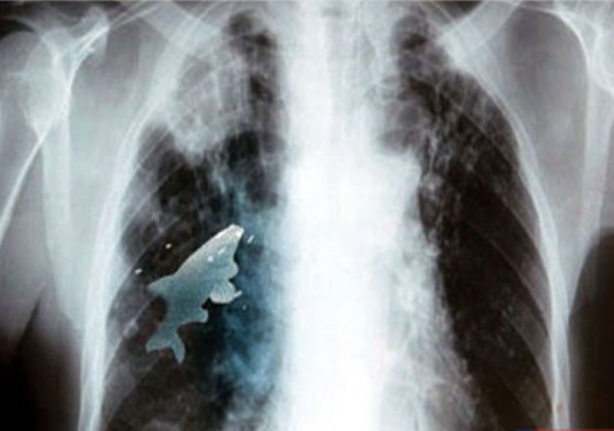

Hindistan'da nehir kenarında arkadaşlarıyla oynayan 12 yaşındaki Anil Barela isimli çocuk, 9 santimetre büyüklüğünde bir balık yuttu.

Balığın sürekli hareket etmesi nedeniyle nefes almakta güçlük yaşamaya başlayan çocuğun kanındaki oksijen oranının da ciddi oranda düşüş göstermesi sonucunda çocuk x-ray cihazından geçirildi. Çekimlerde ciğerlerinde dolaşan balık tespit edilince çocuk hemen ameliyata alındı. Yaklaşık 45 dakikalık operasyonun ardından balık, canlı olarak çıkarıldı.Göğüs hastalıkları uzmanı Doktor Pramod Jhawar, 20 yıllık doktorluk hayatı süresince ilk kez böyle bir durumla karşılaştığını kaydetti.